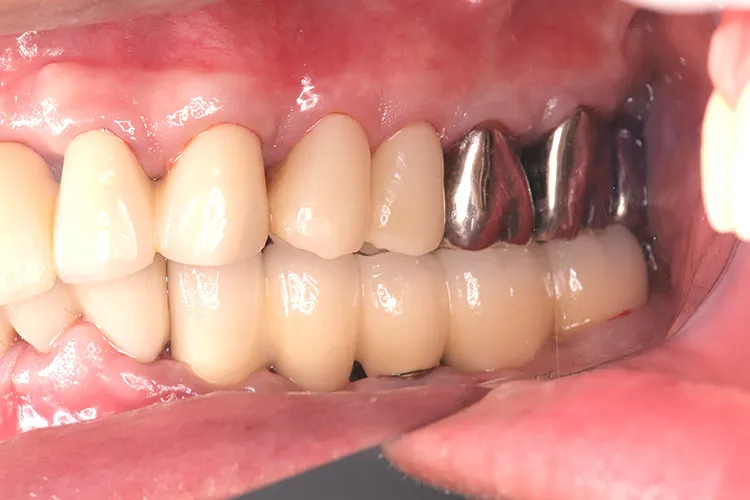

治療前

治療後

レントゲン画像

治療内容

左下5本欠損した部分をインプラント3本埋入して5本ブリッジで治したケースです。なかなかインプラントに踏み切れず、長い間入れ歯を使っておられましたが、噛みごたえがなく好きなものが食べれない上に、度々歯茎が痛んでは調整の繰り返しで快適に過ごすことができず、QOLの向上のためインプラント治療を決断されました。今ではなんでも食べれるとのことで、入れ歯で我慢しないでもっと早くインプラントにすればよかったと言っておられます。